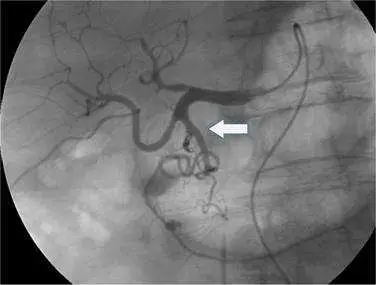

承上題【下圖中箭號所顯示為那一條血管出血? 】附圖,發現出血後所執行之最適合治療應為:

本題考核動脈出血的介入性放射治療選擇。題目為「承上題」的系列題,上題已確認箭號所示為出血血管,本題進一步詢問最適合的治療方式。圖片為數位減影血管攝影(digital subtraction angiography, DSA),可見造影劑外滲(contrast extravasation),確認動脈出血。

圖片為腹腔血管造影(visceral angiography),採用 DSA 技術拍攝。影像特徵如下:

- 造影劑外滲:白色箭頭所指血管周圍可見造影劑在正常血管腔外積聚(blush/pooling),此為急性動脈出血的直接影像徵象

- 血管型態:可見腸系膜或腹腔動脈分支走行,血管迂曲

- 出血灶位置:箭頭指向的活動性出血點,造影劑在組織間隙積聚呈不規則染色

此種 DSA 影像所見的造影劑外滲,是確診急性動脈出血並進行栓塞治療的直接依據。